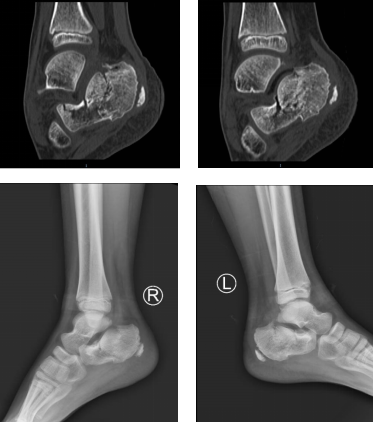

术前片

魏医生给孩子做了仔细检查,患者俩脚跟明显红肿,拍片显示双侧跟骨骨折,断端错位,累及周围关节。考虑到孩子年龄幼小,为了以最小的创伤完成治疗,以最快的速度康复,足踝二病区徐明亮主任和手术小组讨论后决定给孩子施行踝关节镜下微创骨折复位手术。